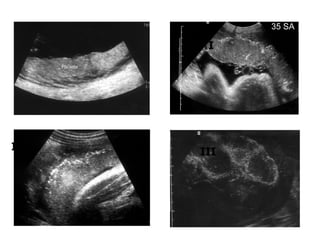

Rau tiÒn ®¹o trung t©m hoµn toµn

M¸u tô sau rau